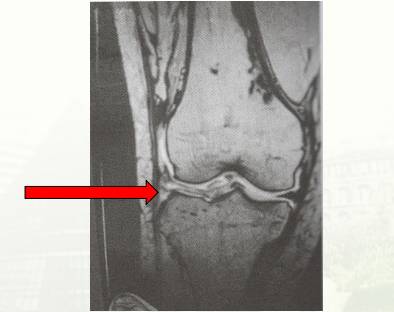

一般医生会选择通过影像学手段诊断。半月板损伤使用MRI的效果最佳,敏感率可达90%-95%,特别是急性期。

正常半月板都是低信号的结构,如果半月板信号中断,取而代之的是高亮信号,则可能是半月板损伤的表现。